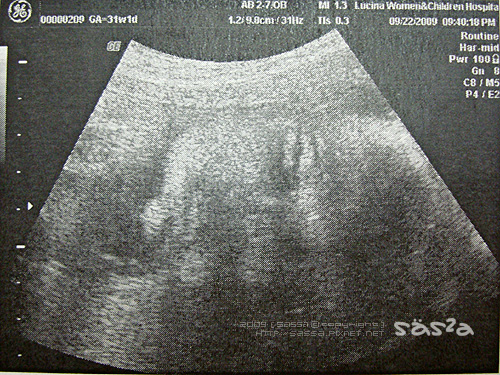

31W1D,昨晚見了小柚子,他跟我想像中的不一樣,希望他是單眼皮+瓜子臉,結果他是個雙眼皮大眼睛,臉形略帶四方福氣的嚴肅莊嚴的面相,我跟柚子拔互問,這孩子像誰?哈哈哈!柚子拔還說『這麼說很不敬,就覺得小柚子長得有點像彌勒佛!』XDDD。

鼻子嘴巴像拔鼻

這次產檢小柚子成長到1559g(上次產檢1436g),我問醫生小柚子會不會太輕,醫生說在標準內,不輕也不重。我這媽兩周重了一公斤,也在標準內,我不禁想問,為娘我重一公斤,小柚子才重123g,那剩下的900g不就是肥在我 @#%&